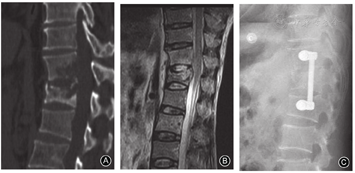

椎体骨破坏是支持脊柱结核的有力证据[13]。结核患者椎体骨破坏比较严重,椎体内形成明显的死骨,因此外科手术时往往选择椎体次全切除进行清创和重建(图4);而化脓性脊柱炎患者的骨破坏往往局限在终板周围,外科手术时更多选择椎间盘连同软骨终板和周围死骨切除清创后,行椎间隙植骨融合(图5)。有学者分析了33例结核和33例化脓性脊柱炎患者,结果显示54.5%化脓性脊柱炎患者椎体无破坏或轻度破坏(<25%),而结核患者椎体破坏几乎是100%;仅6%化脓性患者椎体破坏>75%,而结核患者比例高达45.4%[9]。所有结核患者均存在椎体骨皮质破坏或丢失,而仅39.3%化脓性脊柱炎存在骨皮质破坏[9,14]。